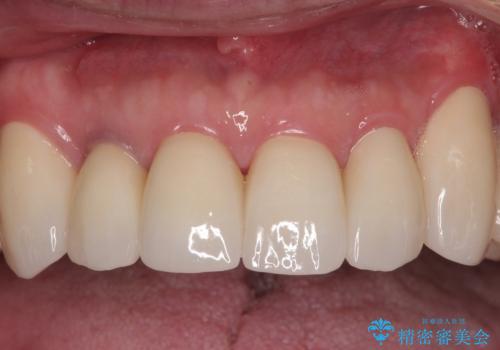

欠損部はインプラントによる補綴治療を行うこととし、臼歯部が安定した後に、上下前歯部をオールセラミッククラウンにて補綴治療を行うこととしました。

上顎前歯に歯周ポケットの深い部分がありましたが、インプラントの仮歯で奥歯がしっかりと噛めるようになると、1年程度で深い歯周ポケットは解消されました。

前歯部の審美面も大幅に改善され、大変満足していただけました。